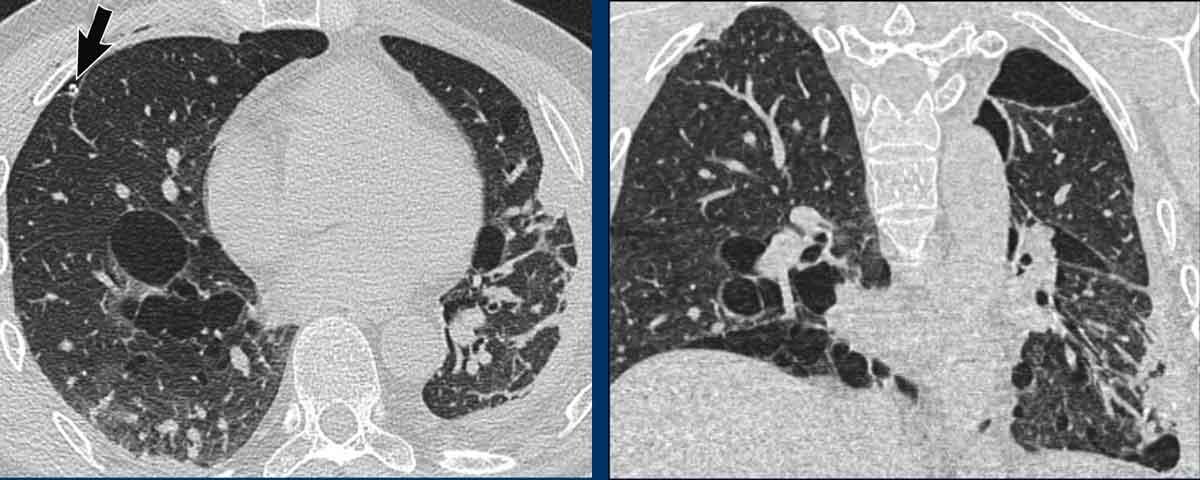

LAM biểu hiện với số lượng lớn các nang hình tròn, bờ đều đặn, phân bố rải rác khắp nhu mô phổi.

Hình ảnh

- Nhiều nang ở một phụ nữ trẻ. Lưu ý hình dạng tròn đều và phân bố lan tỏa.

- Trường hợp LAM nặng. Khi có tiền sử hút thuốc lá, chẩn đoán phân biệt cần đặt ra là LCH (giai đoạn tiến triển).

- Tràn dịch màng phổi (dịch dưỡng chấp) ở bệnh nhân LAM.

- Phân bố lan tỏa trong LAM.

Các hình ảnh này thuộc về một phụ nữ 39 tuổi với triệu chứng khó thở.

Chẩn đoán có khả năng nhất là gì?

Nhận xét hình ảnh

Có nhiều nang thành mỏng.

Lưu ý các nang phân bố đều khắp hai phổi.

Các ngách màng phổi cũng bị tổn thương (mũi tên).

Điều này cho phép loại trừ chẩn đoán LCH.

Chẩn đoán có khả năng nhất là LAM.

Đây là một ví dụ khác của LAM.

Có nhiều nang thành mỏng phân bố đều khắp hai phổi, điển hình cho LAM, nhưng trong trường hợp này kết hợp với tràn dịch màng phổi bên phải (mũi tên).

Các tế bào LAM có thể gây tắc nghẽn hệ thống bạch huyết trong lồng ngực và tạo ra tràn dịch màng phổi dưỡng chấp.

LAM là bệnh phổi dạng nang duy nhất có thể thấy sự kết hợp giữa các nang và tràn dịch màng phổi.

Ngoài ra, nhiều u cơ mỡ mạch máu (angiomyolipoma) được phát hiện ở vùng bụng trên.

Bệnh nhân này được xác định mắc LAM liên quan đến phức hợp xơ cứng củ (TSC – tuberous sclerosis complex).

Tỷ lệ hiện mắc u cơ mỡ mạch máu trong LAM tản phát là 40-50% và trong LAM liên quan TSC vào khoảng 80%.

Đây là trường hợp LAM nặng với nhu mô phổi bị tổn thương lan tỏa.